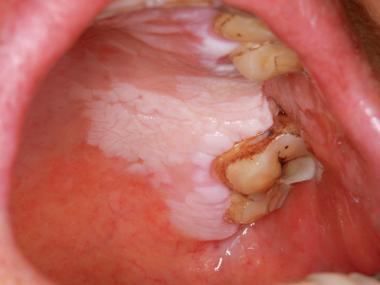

“白色较硬的隆起斑块”这个描述,指向性比较强,可能涉及多种口腔疾病,从相对良性的到需要高度警惕的都有,以下是一些主要的可能性,按常见程度和危险程度进行排列:

这是最常见的原因之一,是口腔粘膜上以白色为主的损害,不能被擦掉,也没有其他任何主观症状(如疼痛)。

- 形态:表现为白色或灰白色的斑块,可以是平的,也可以是轻微隆起的,质地较硬,表面可能粗糙、有皲裂,也可能呈皱纹纸状。

- 部位:最常见于颊粘膜(内侧)、牙龈、舌腹(舌下面)等部位。

- 危险性:口腔白斑本身是癌前病变,虽然大部分白斑终生不会癌变,但有少数(尤其是伴有“疣状增生”或“颗粒型”外观的)存在一定的癌变风险。必须由医生评估其风险等级。